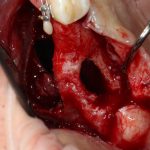

Подготовка костного ложа и фиксация аутотрансплантата

Возвращаемся к основной операционной области. Еще раз посмотрим на альвеолярный гребень, поофигеваем от его ширины и моих грандиозных планов:

Я зафиксировал костный блок практически без адаптации на несколько винтов. Обрати внимание, что винты находятся в зоне, где не планируется установка имплантатов. Фиксация должна быть надежной, поскольку мне еще предстояла подготовка лунок для имплантатов. Трех винтов для этого вполне достаточно.

Дальнейшая адаптация костного блока свелась к сглаживанию острых краев. После чего я приступил к подготовке лунок и установке имплантатов.